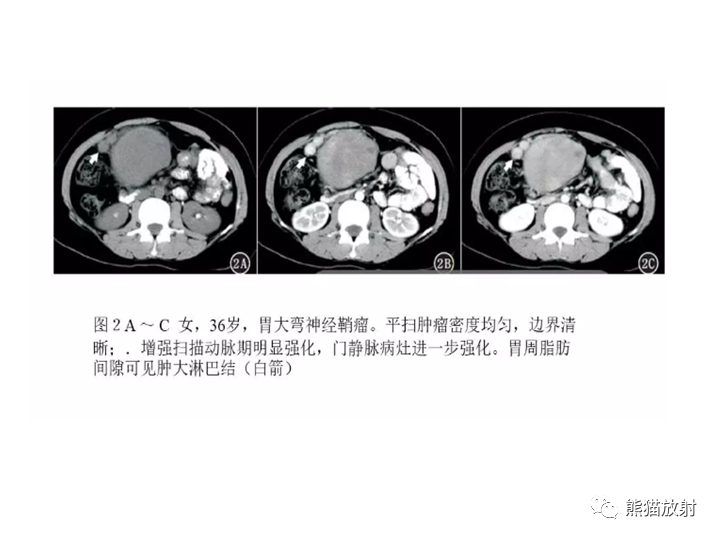

【病例】胃间质瘤VS神经鞘瘤-3